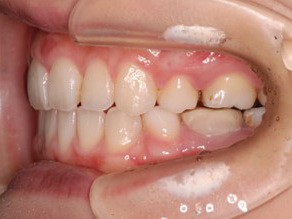

永久歯に交換するためのスペース不足による前歯のガタガタで、取り外しができる拡大床にて上下顎の幅を拡大した後、上顎の前歯をマルチブラケット装置で並べました。治療の期間は1年9か月でした。

初診時